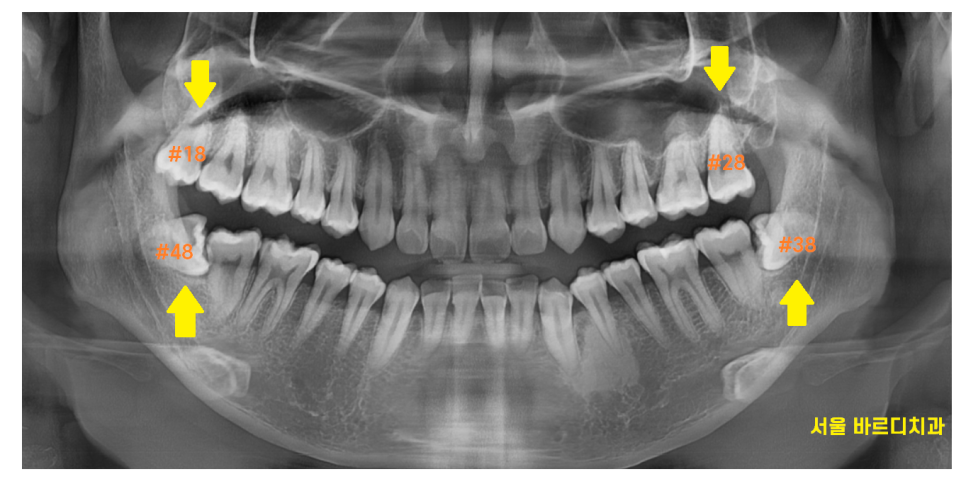

사진 속 4개의 사랑니가 있는데요.

한눈에 보기에도 아래쪽에 위치한 사랑니는

누워있죠~?

누워있고 숨어있는 사랑니는

발치 난이도가 증가하지만

예쁘게 잇몸 밖으로 올라온 사랑니,

윗니 사랑니는 수월하게 뽑을 수 있습니다 .

이렇게 누워서 난 사랑니는

수직으로 뽑을 수가 없기 때문에

쪼개서 뽑아야합니다.

발치 난이도도 올라가고

뼈도 삭제해야해서

발치 후 통증이 심할 수 있습니다.